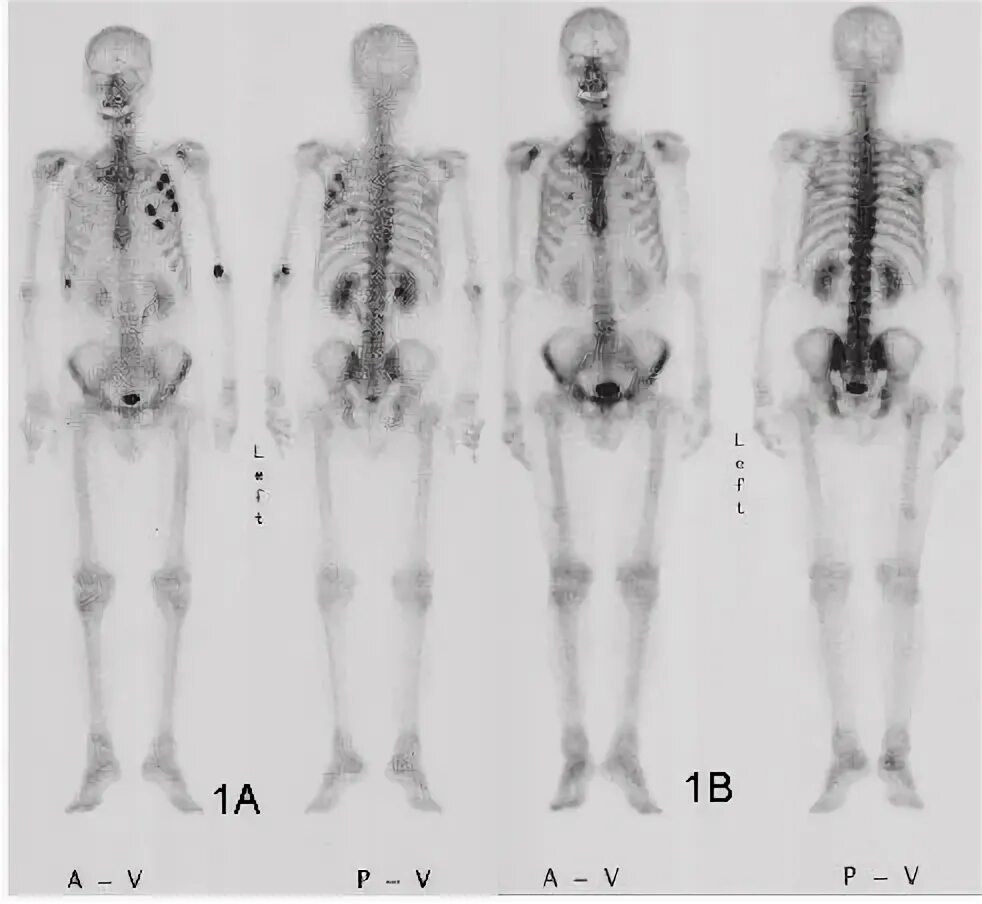

Метастазы скелета